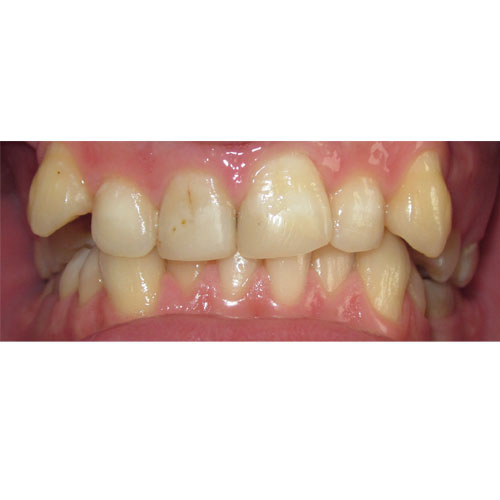

Nasze rezultaty